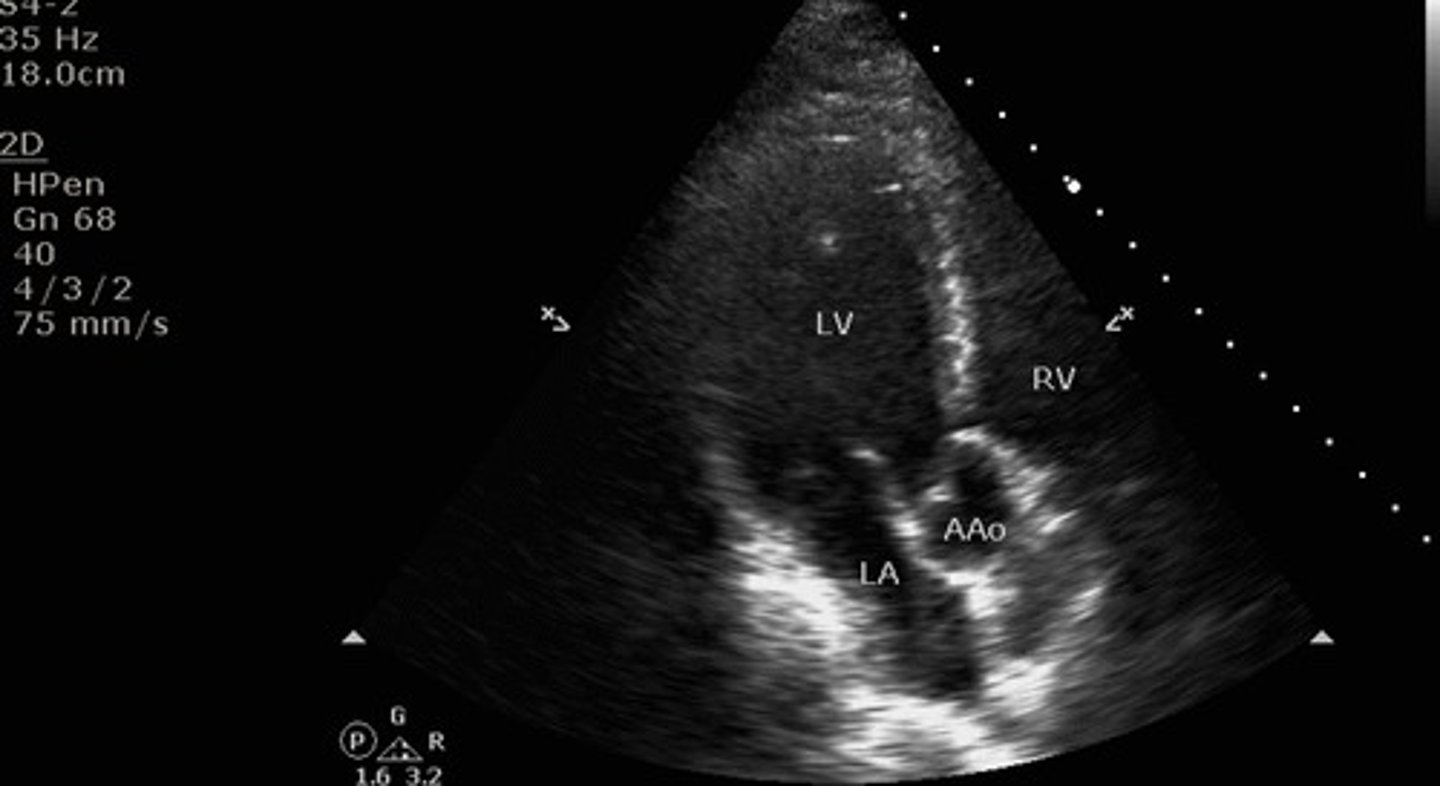

apical 3 chamber view

what view is this?

LV, RV, outflow tract, mitral valve, aortic valve, ascending aorta, descending aorta

what structures are seen with apical 3 chamber view?

parasternal long axis and apical 3 chamber view

what two views have the same structures?